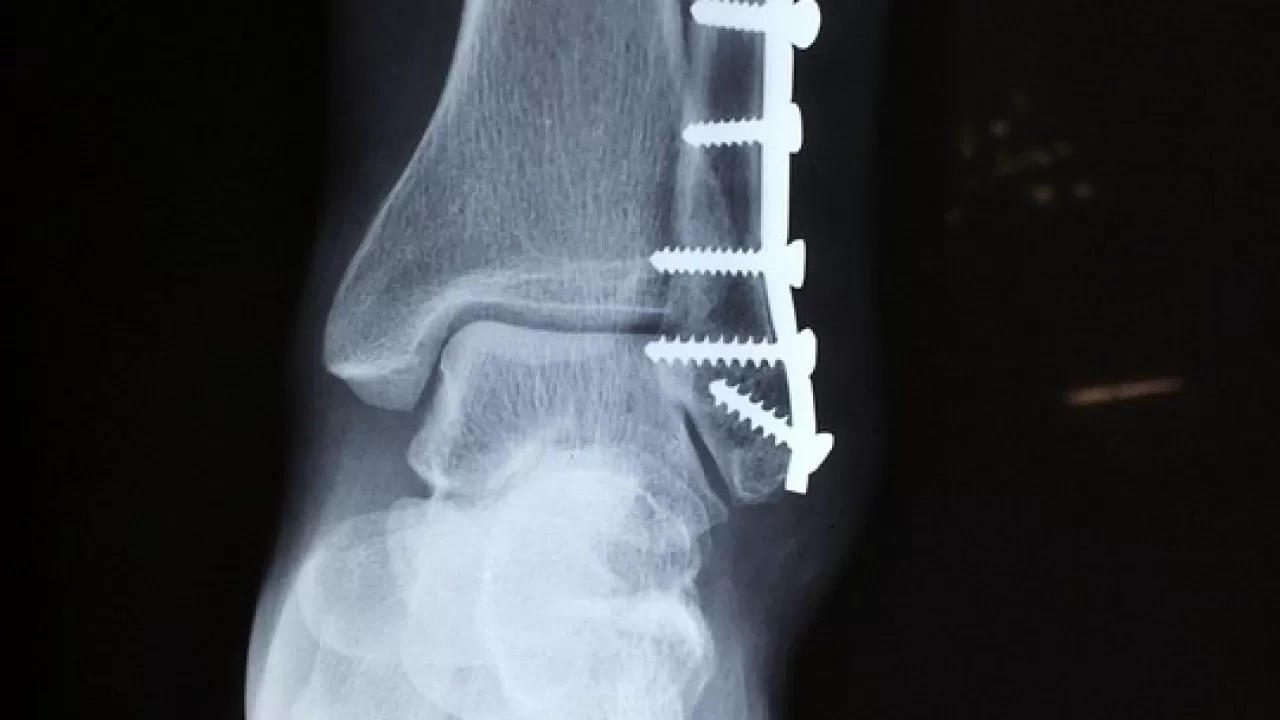

Стержень аппарата внешней фиксации для остеосинтеза разработали и запатентовали специалисты Тюменского медицинского университета. Проведенные исследования показали, что этот образец обеспечивает хорошую остеоинтеграцию (фиксацию стержня в кости). Это играет важнейшую роль при лечении пациентов с переломами на фоне остеопороза, inbusiness.kz со ссылкой на пресс-службу ТМУ.

Как пояснили в пресс-службе ТМУ, оперативное лечение усложняется тем, что костная ткань вокруг установленной металлоконструкции подвергается повышенной резорбции (рассасыванию), что не обеспечивает прочную фиксацию отломков, затрудняет сращение перелома и дальнейшее восстановление пациента.

"Запатентованный стержень имеет технические характеристики, соответствующие современным тенденциям. Ключевым преимуществом является использование авторского синтетического биоактивного покрытия. Оно представляет собой кальций-фосфатный минеральный комплекс, дополненный биогенными элементами, нанесенный на титановый стержень, что повышает сродство с костной тканью. Биоактивное покрытие снижает резорбцию (рассасывание) в периимплантационной зоне, обеспечивая стабильность установленного стрежня в послеоперационном периоде", - пояснил соавтор патента, директор университетского НИИ медицинских биотехнологий и биомедицины ТМУ Александр Марков.

"Изначально металлоконструкция разрабатывалась для лечения дистального метаэпифиза лучевой кости, однако концепция позволяет применять ее при любых видах повреждений и в любых аппаратах внешней фиксации. Для этого создан размерный ряд cтержней от 4,2 до 11 миллиметров в длину", - говорится в сообщении.